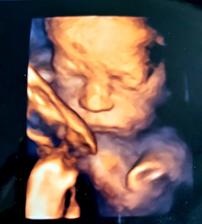

Druhé šťastie